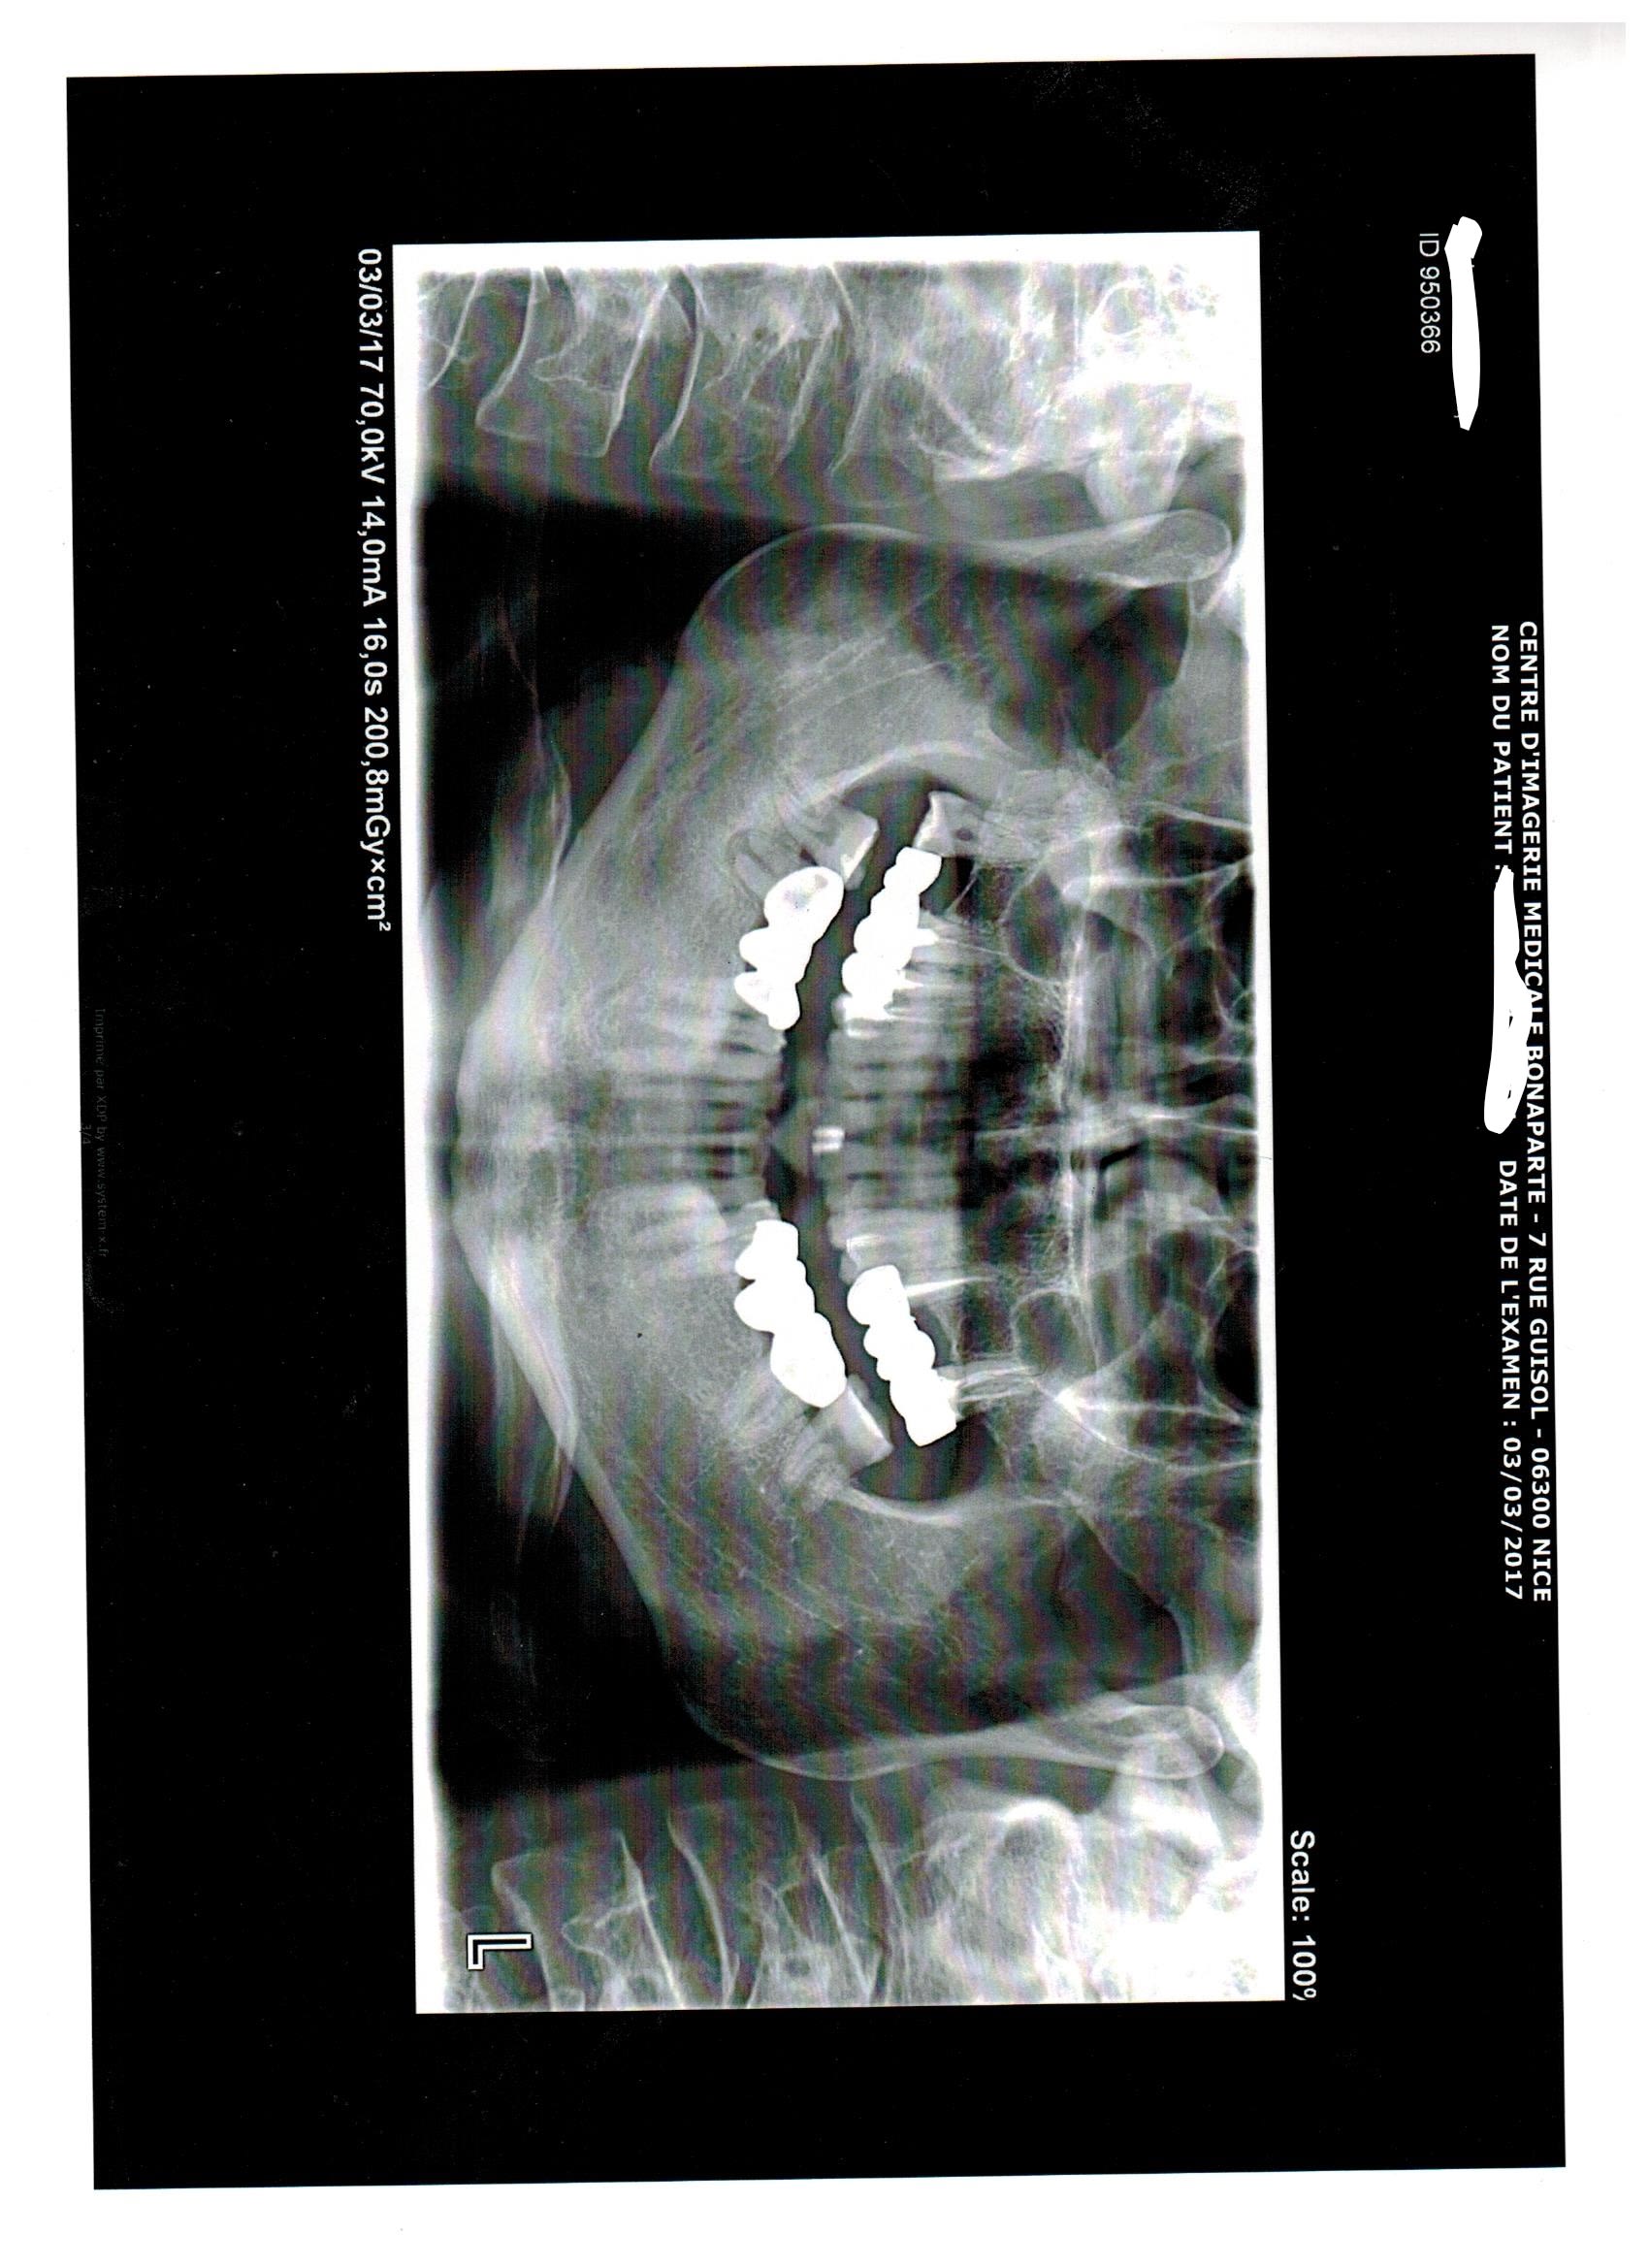

Un patient qui souffre depuis environ 1 an, une a deux fois par semaine le soir vers 17-18h de grosses douleurs diffuses non pulsatiles (maxillaire sup gauche, sinus, oeil, derriere le crane, bref toute la partie gauche mais le centre de la douleur est selon lui localisé au dessus de la 24/25).

Bref, je me suis dis que ca devait venir de 25 ou 27, donc j'ai repris les deux traitements dans les règles, mais aucune amelioration, il y avait aussi une petite carie sur la 24, mais de la a avoir de grosses douleurs pendant 1 an j'y crois pas trop.

Au passage je vous poste le scan réalisé:

L'image plus visible ... qui objective aussi une fracture de la racine Distale de 27.

Tu dis dans ton poste que tu as repris les traitements du secteur 20 pour ensuite dire que le bridge a une vingtaine d'années. Comment as tu fait ds ce cas pour entreprendre une rte sur 27 avec apparemment un inlay core ?... Ce que je vois sur ta pano c'est surtout 2 fractures radiculaires: une au tiers coronaire de la racine mesio vestibulaire juste à l apex du tenon l autre au tiers apical de la 25...sans parler de la grosse lésion sur la racine distale qui ressemble plus à une énorme carie sous la couronne qu'à une résorption externe.

Peut etre pour 25 un artefact? (variation brutale de densité liée au modelé osseux)?

EDIT: en regardant bien, la solution de continuité radiculaire me parait bien importante pour un artefact. La probabilité de fracture horizontale au tiers apical radiculaire est importante!

Oui je suis d'accord j'ai regardé à plusieurs reprises et c'est plus de l'ordre de la fracture ;autant sur 25 que sur la 27. Les piliers du bridge en l'état ne sont plus conservables. Pour le moment cela se manifeste par des douleurs mais d'ici quelques temps d'autres symptômes s'en suivront notamment lorsque la 27 va commencer par lâcher il va apparaître un abcès en vestibulaire juste en regard de la racine mesio vestibulaire ou peut-être en regard de l'espace inter radiculaire et non au fond du vestibule. C'est l'affaire de quelques mois. Il vaut mieux temporiser jusque là et confirmer le diagnostic. Auquel cas il faudra tout déposer et envisager l'extraction des 2 piliers.

Alors il est vrai que la pano est trompeuse mais:

Il n'y a pas d'IC ni sur la 25 ni sur la 27, et pour reprendre les traitements j'ai pu deposer le bridge a l'arrache couronne (je sais c'est pas bien mais sinon fallait flinguer le bridge et monsieur avait pas les sous pour tout refaire)

Il n y a pas non plus de fracture que ce soit sur la 25 ou la 27, a mon avis l'image sur la 7 c'est du a la corticale, pour la 25 je l'explique pas mais j'ai les retro au cab et RAS, meme ce qui semble etre une carie en distale de la 7 be non, d'ailleurs cette radio transparence n y etait pas sur les retros... (qui sont au cab mais la c est le week end donc repos)

J ai une petite preference pour la piste occlusale, je vous tiens au jus et continue a lire vos recommandations, merci les gars! (et meme les filles hein (= )

Des images radios quasi evidentes sur la pano qui n'apparaissent pas sur les retros surtt sur la 27 c'est qu'ils règlent très mal les appareils à Nice ! ou c'est ta rvg qui contraste mal...poste nous les retros je veux vraiment voir.